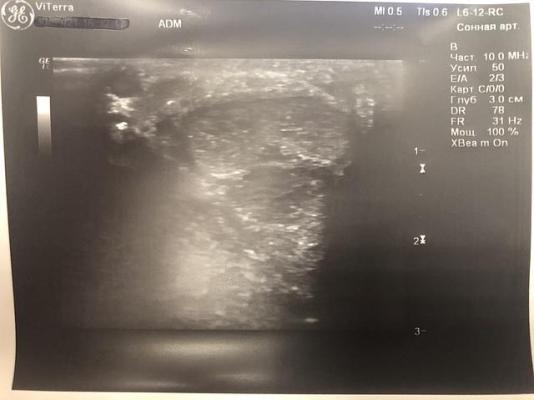

При УЗИ полового члена: определяются гиперэхогенные включения с чёткой эхо-тенью в проксимальной трети дорзально 3х1.5 мм и между кавернозными телами 3.3х2 мм (фрагменты исходной бляшки), дистально - два включения 2х1 мм дорзально и три от 1.5 до 3 мм между кавернозными телами.